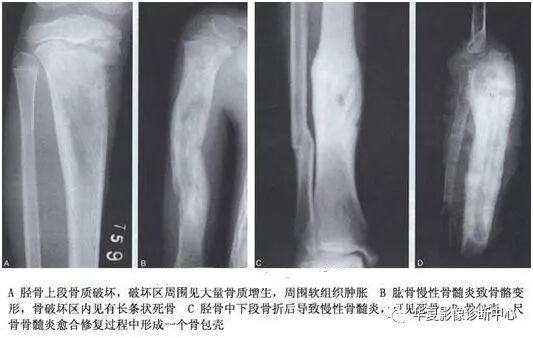

异常骨化有两种表现形式:骨质增生硬化和肿瘤骨。

骨质增生硬化:表现为局部的骨质密度增高,皮质增厚变形,局部骨小梁的增多、增粗,骨髓腔狭窄、甚至消失或形成骨赘。

肿瘤骨:在病灶内或软组织肿块内,是由病理性成骨组织形成的骨质,不能演变为正常的骨质结构。表现为骨内或(和)软组织肿块内云絮状、斑块状、放射状无证正常骨小梁结构的高密度影,其密度可以差异很大。

反应性骨质增生硬化与肿瘤骨最大的不同在于前者在病灶的周围,是由正常的成骨细胞形成的骨质,可演变为正常的骨结构;后者则在病灶内或软组织肿块内,是由病理性成骨组织形成的骨质,不能演变为正常的骨质结构。

骨质坏死:是骨组织局部代谢的停止,坏死的骨质称为死骨。

死骨形成的原因主要是血液供应的中断。组织学上的表现是骨细胞死亡、消失和骨髓液化、萎缩。早期,骨小梁和钙质含量无何变化,此时X线上也无异常表现。当血管丰富的肉芽组织向死骨推进,则出现破骨细胞对死骨的吸收和成骨细胞的新骨生成,这一过程延续时间很长。

死骨的X线表现是骨质局限性密度增高,其原因有二:其一是周围骨质疏松,死骨相对性的密度增高;其二是死骨骨小梁表面有新骨形成,骨小梁增粗,骨髓内亦有新骨形成,即绝对的密度增高。死骨的形态因疾病的发展阶段不同而不同,随着病程的延长,死骨可逐渐被吸收。恶性肿瘤的残留骨有时为死骨,有时为活骨。